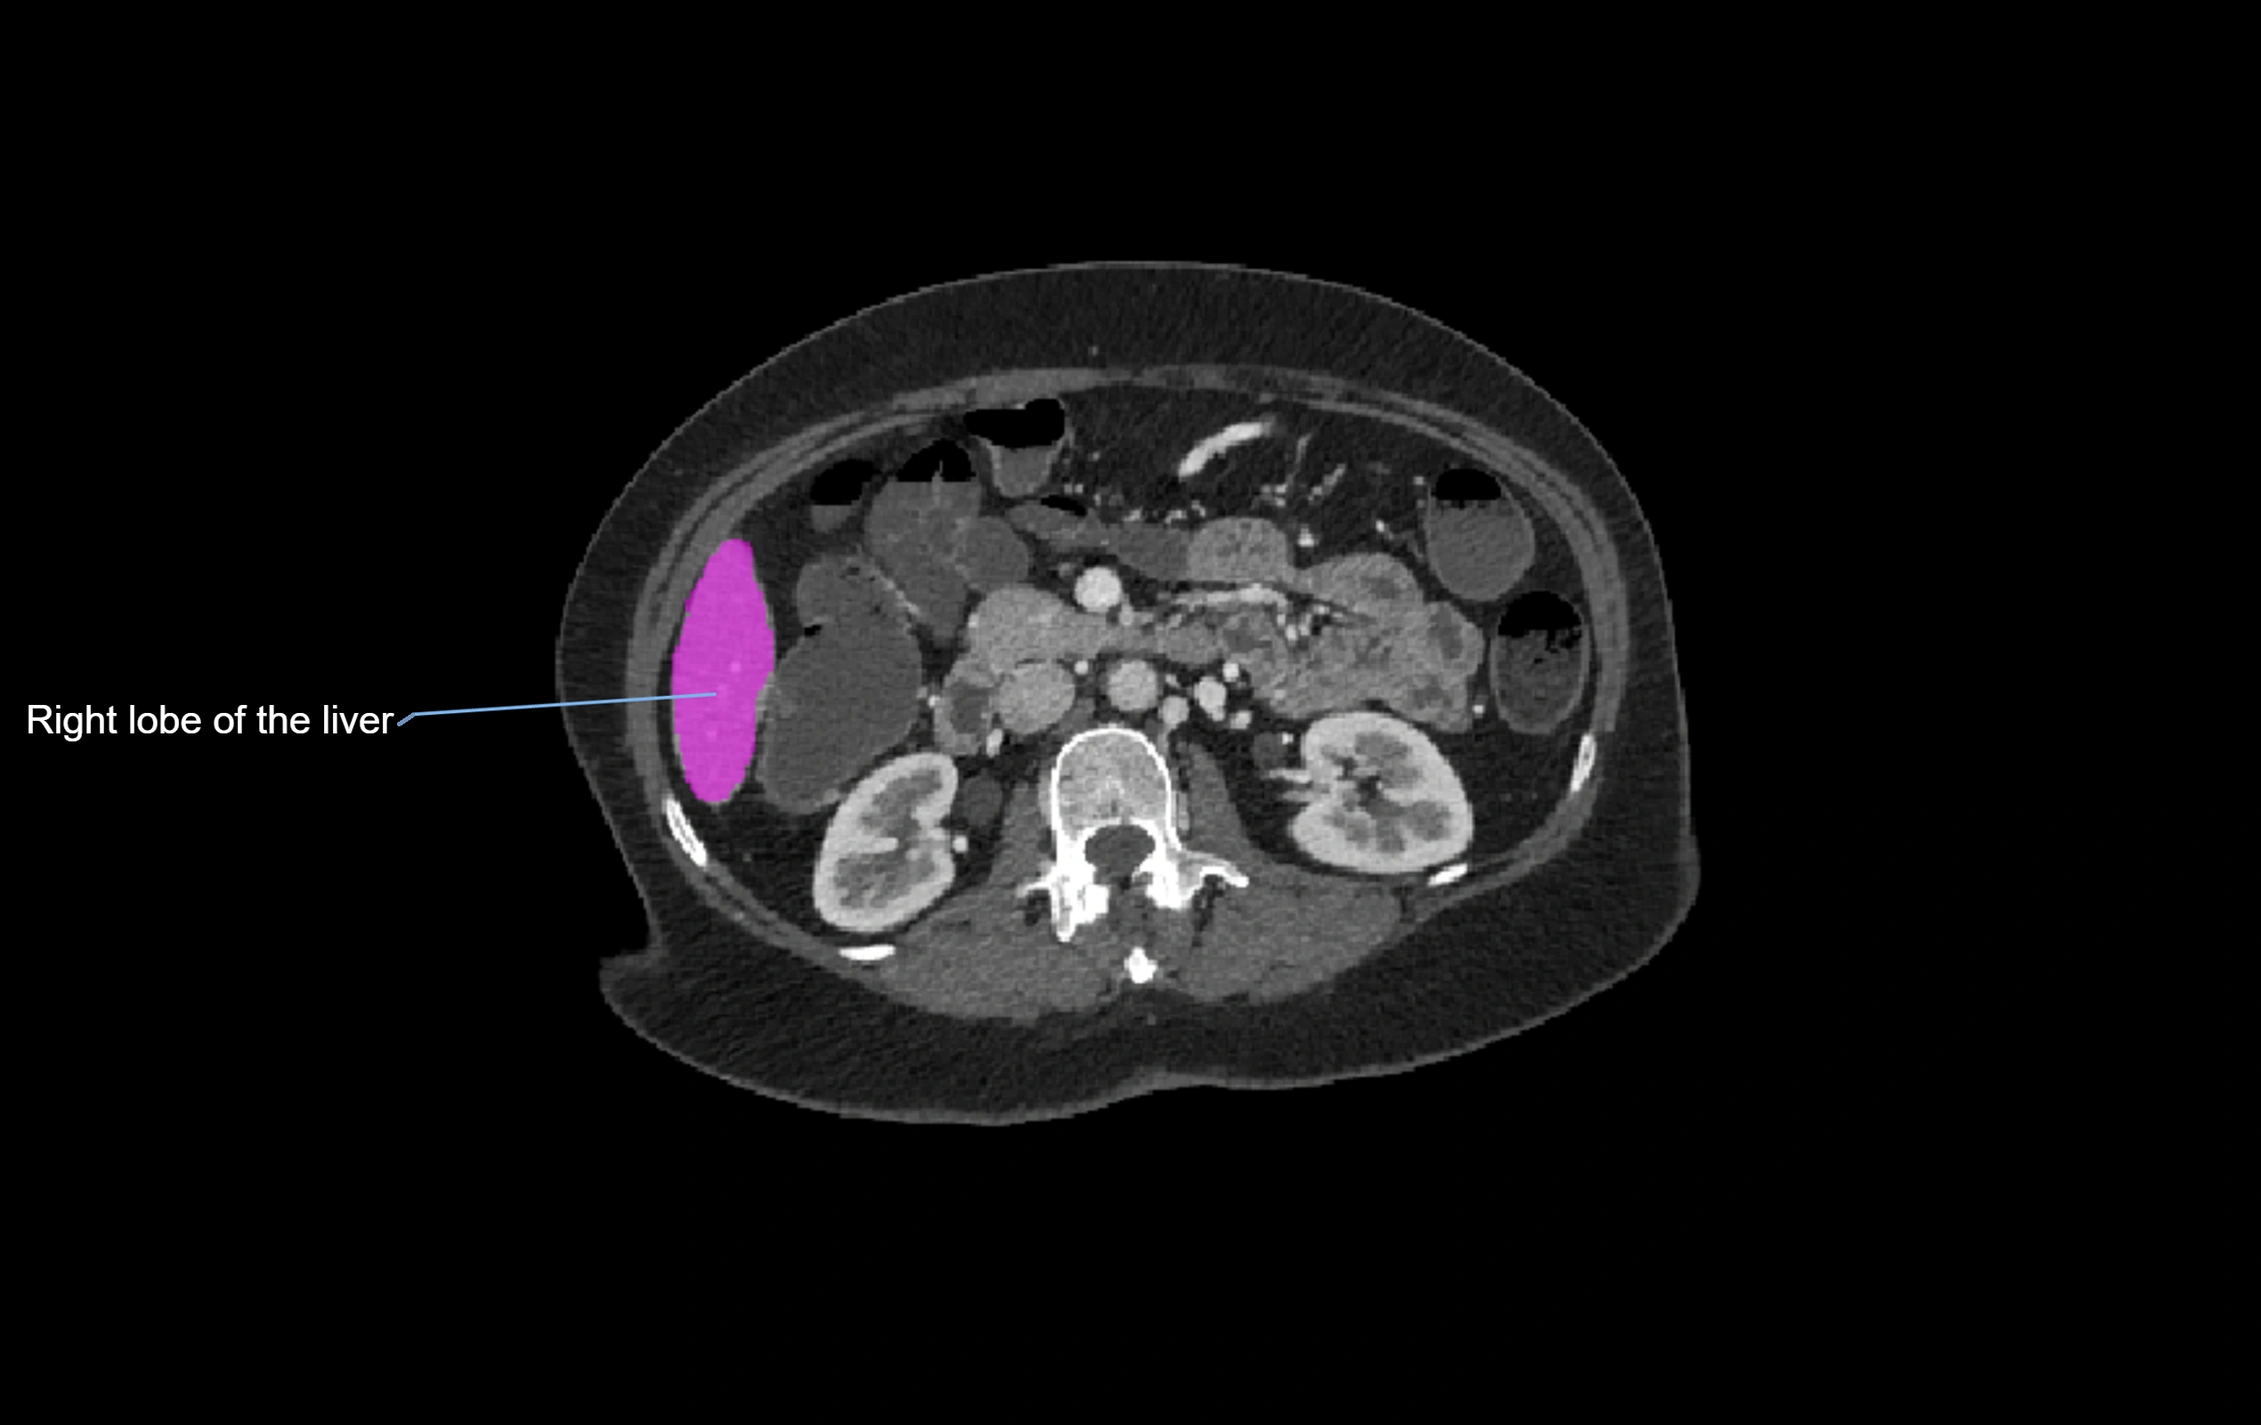

CT Appearance

CT Pre-Contrast:

• Caudate lobe appears as a soft-tissue density, isodense to the rest of the liver

• Enlargement may be appreciated in cirrhosis or Budd–Chiari syndrome

CT Post-Contrast:

• Homogeneous enhancement in the portal venous phase, similar to rest of liver

• Independent venous drainage into the IVC may be visualized

• Lesions follow characteristic CT enhancement patterns (HCC: arterial hyperenhancement with washout; hemangiomas: peripheral nodular enhancement with centripetal fill-in)

CT Venous Phase (functional significance):

• Caudate lobe often enhances relatively more than other lobes in Budd–Chiari syndrome, due to preserved venous outflow

CT Image

image